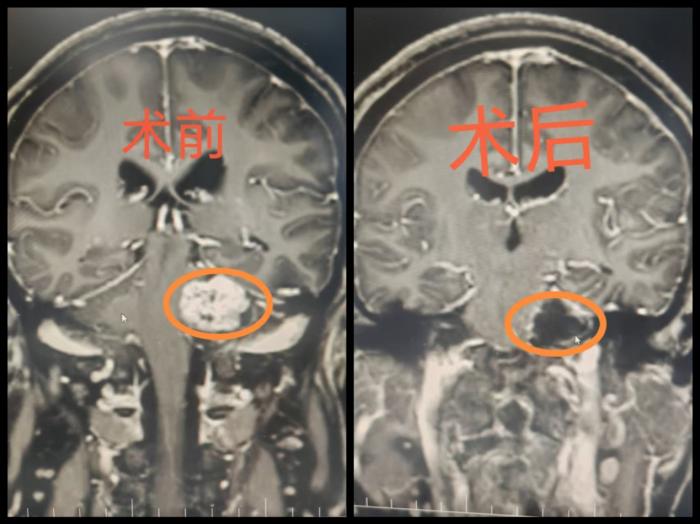

最终,两人在湘南学院附属医院神经外科找到“元凶”:影像检查显示,雷先生颅底静脉孔区藏着一颗乒乓球大小的神经鞘瘤,已严重压迫脑干;张阿姨的听神经瘤则像枣核般卡在耳道深处,紧紧包绕听神经与面神经。两位老人分别被确诊为罕见静脉孔神经鞘瘤与听神经瘤,需尽快手术摘除肿瘤。

颅底肿瘤手术堪称“在刀尖上跳舞”,两位患者的肿瘤与关键神经紧密缠绕,剥离时稍一用力就可能造成永久神经损伤。面对挑战,罗忠平主任医师带领团队启用神经电生理实时监测、3D影像导航等尖端技术,在显微镜下开展“微米级”精细操作,分别为雷先生和张阿姨,完整剥离肿瘤,精准避开重要神经,成功保全机体功能。